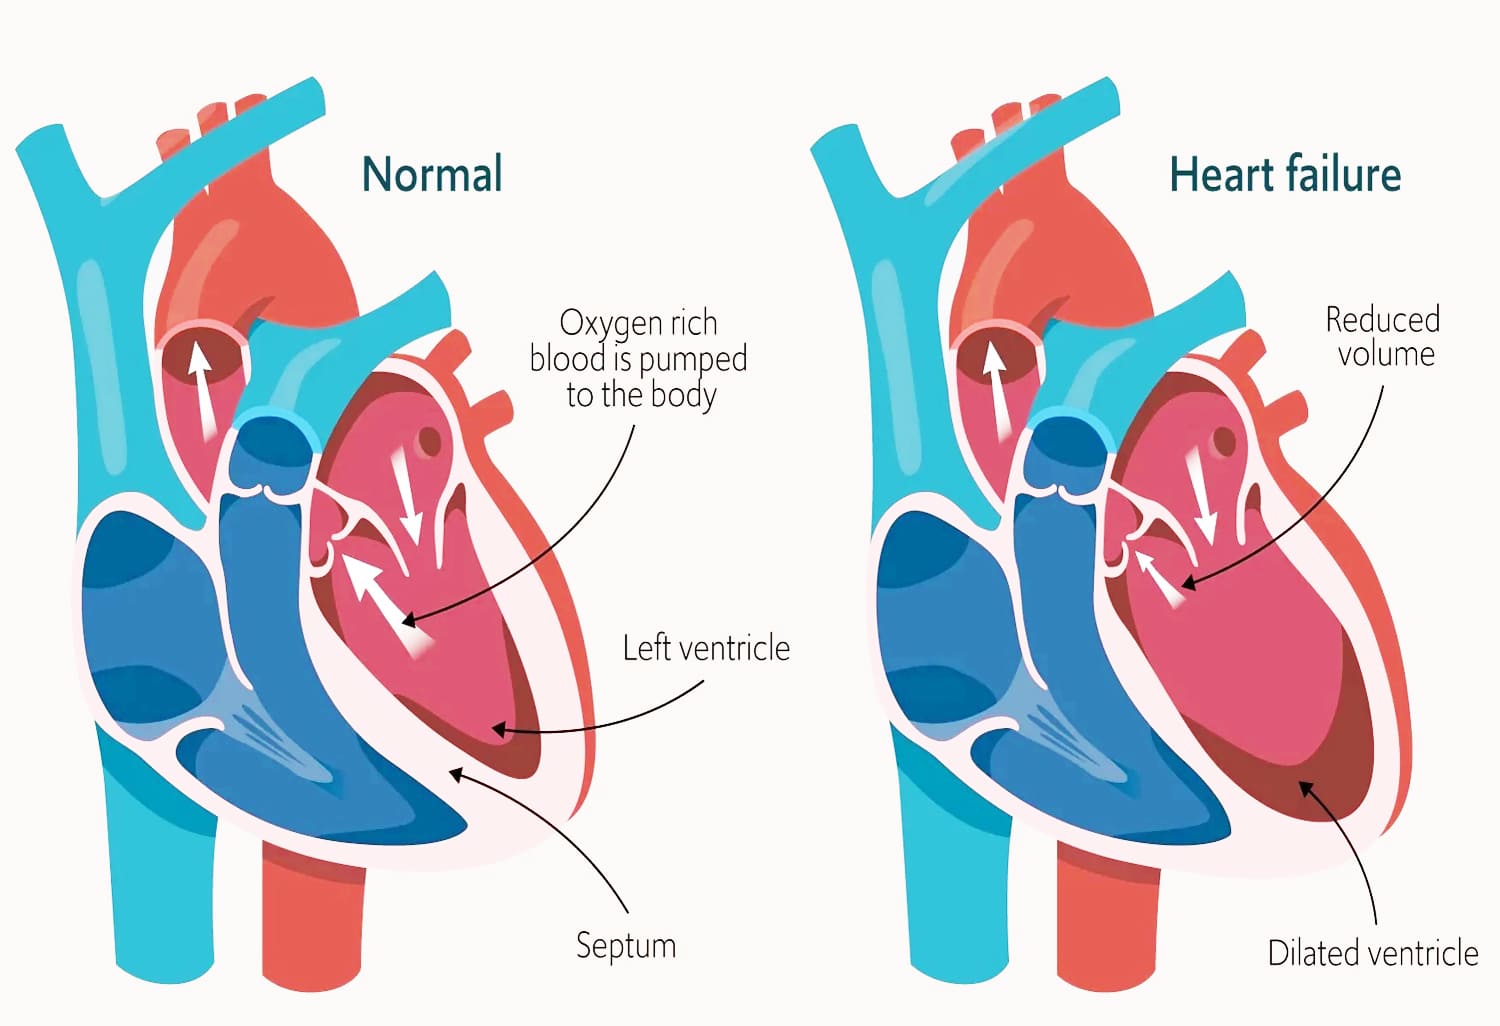

Pria atau wanita kategori anak-anak, remaja, dewasa, orang tua dan manula bisa mengalami serangan jantung secara tiba-tiba.

Gangguan pada jantung dapat terjadi secara tiba-tiba dan memerlukan perhatian yang serius. Keluhan seperti nyeri dada akibat hambatan aliran darah perlu ditangani dengan pendekatan yang tepat dan terukur.